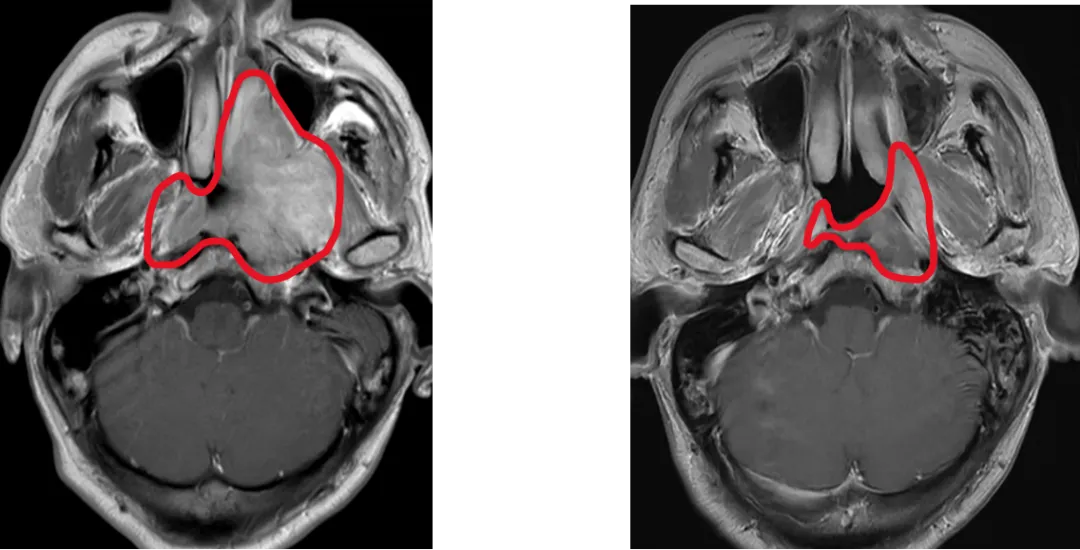

鼻咽癌高发于中国,新发病例占全球47%。放射治疗是鼻咽癌的根治手段,但中晚期患者需要在放疗前接受化疗,放疗前化疗使90%患者肿瘤缩小,而既往国际指南推荐放疗照射范围仍需包括化疗前肿瘤大小覆盖的范围,导致周围正常组织(如内耳、腮腺)接受高剂量辐射,引发听力损伤、口干等不可逆副作用,严重影响患者生活质量。

为此,马骏院士团队展开有关研究,采用了国际通用的标准多中心、随机、平行对照设计,纳入445例中晚期鼻咽癌患者,随机分为两组:分别基于化疗后和化疗前肿瘤范围进行放疗。主要终点为3年局部区域无复发生存率,次要终点包括毒副反应和生活质量。

这项多中心III期临床试验证实,仅照射化疗后的肿瘤范围,并没有增加复发,却显著降低了毒副反应,显著改善患者生活质量,使我国鼻咽癌诊疗实现从“保生存”到“优生存”的跨越式突破。3年局部区域无复发生存率达91.5%(与传统疗法持平);严重放射性口腔黏膜炎降低4成,晚期严重中耳炎发生率锐减5成,口干症状改善6成;整体健康状态、体力状态、情绪功能显著改善,口干及唾液黏稠症状减轻。